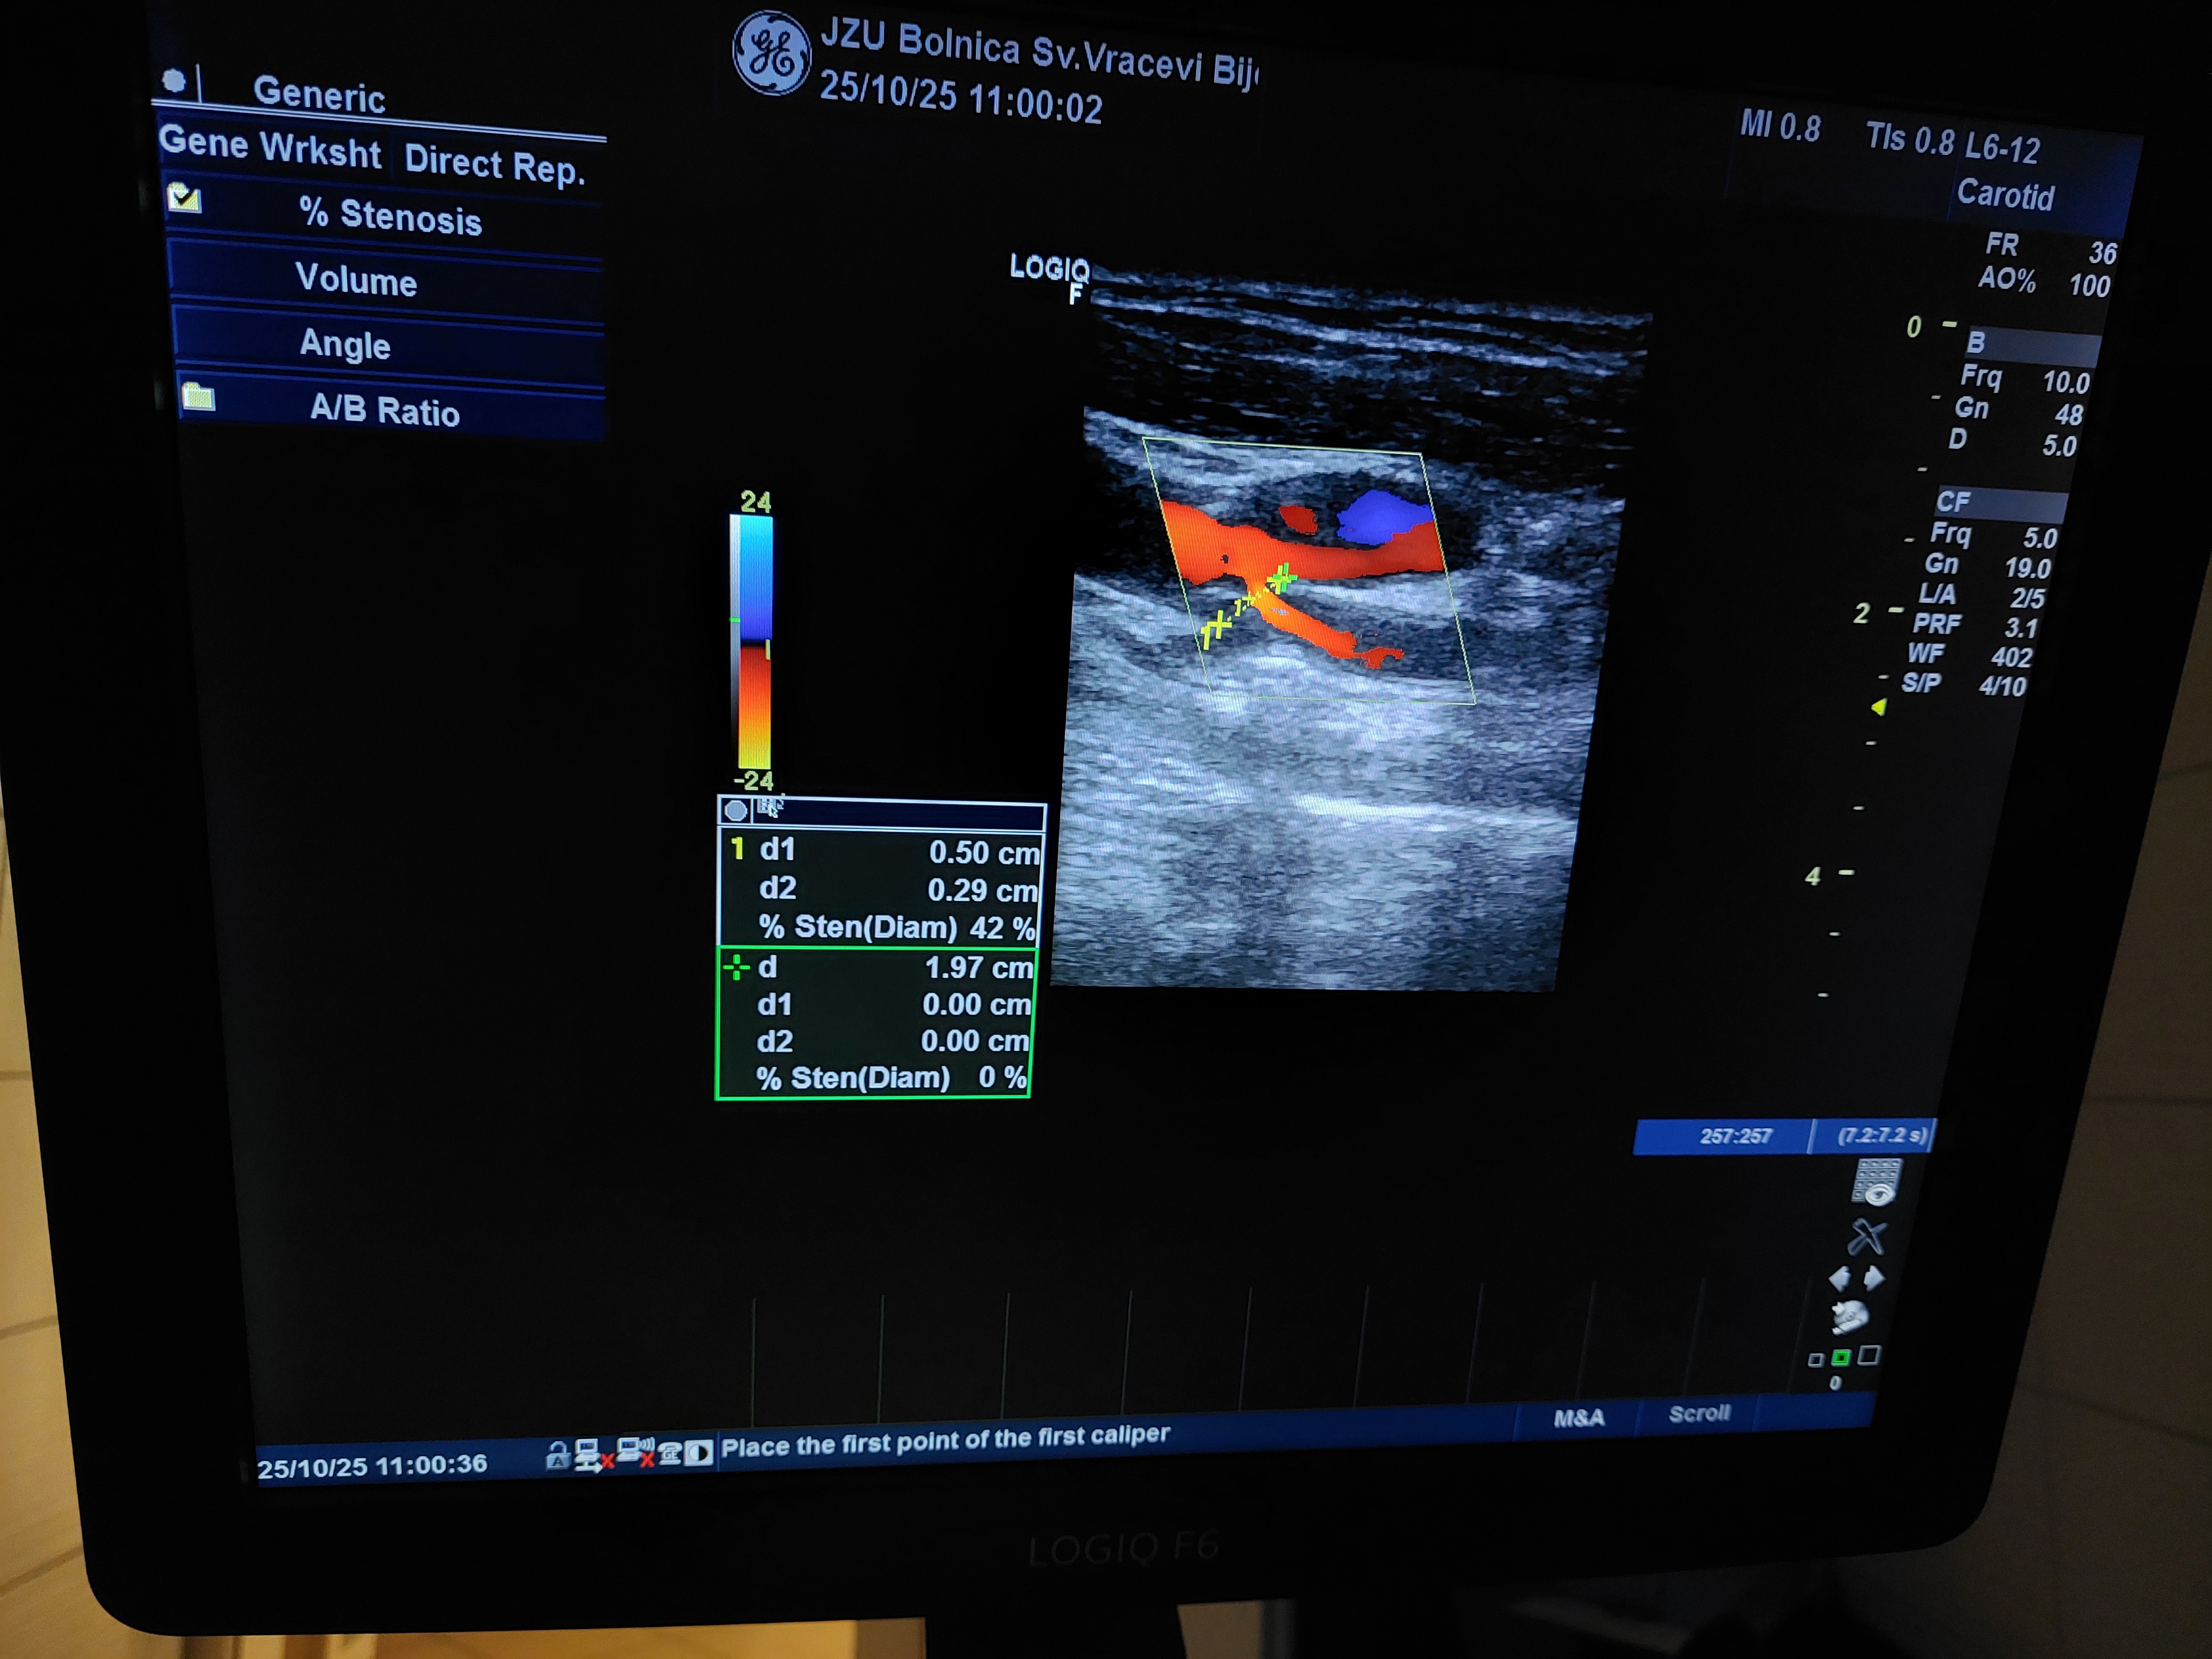

U susret Svjetskom danu moždanog udara, koji se obilježava 29. oktobra, Odjeljenje za neurologiju JZU Bolnica “Sveti Vračevi” Bijeljina organizovalo je u subotu, dodatne kolor dopler ultrazvučne preglede krvnih sudova vrata za 50 pacijenata koji imaju potrebu za ovom dijagnostičkom metodu.

Odjeljenje neurologije raspolaže savremenom dijagnostičkom opremom za EEG, EMNG i kolor dopler ultrazvučne preglede krvnih sudova vrata i mozga, a stručni tim čine iskusni neurolozi i medicinsko osoblje posvećeni stalnom unapređenju dijagnostike, terapije i rehabilitacije pacijenata.